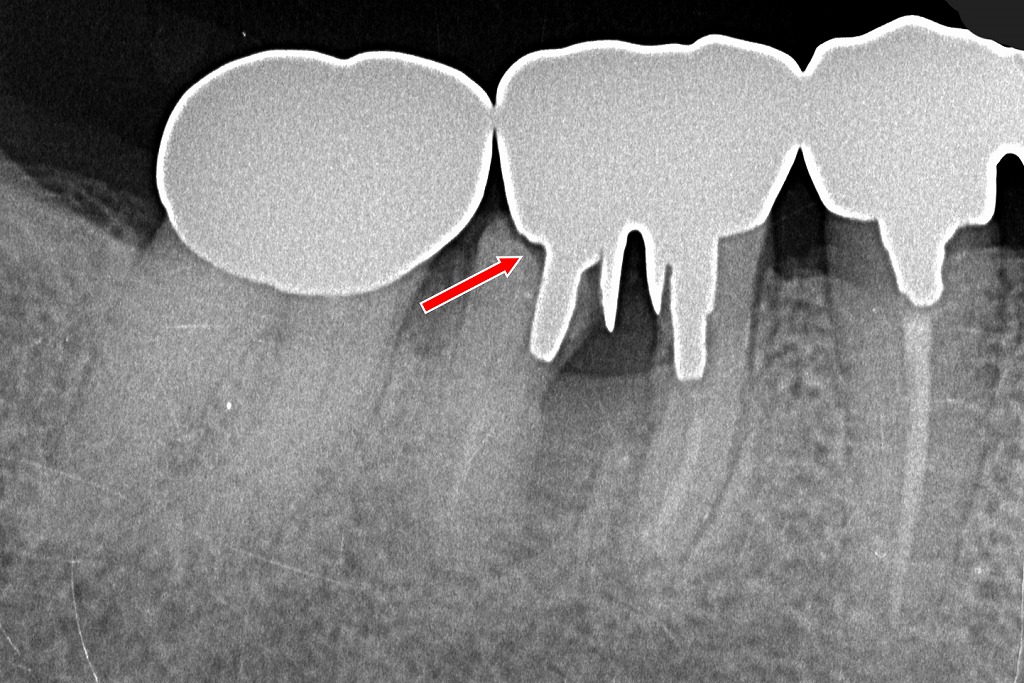

⑥7番と5番を支台とした3歯ブリッジの装着後X線像

このX線写真には、右側臼歯部(7番・6番・5番)にブリッジが装着されている状態が示されています。

7番と5番が支台歯

画像左側の**7番(第二大臼歯)と右側の5番(第二小臼歯)が支台となり、

その間の6番(第一大臼歯)の位置にダミー歯(ポンティック)**が設定されています。

これは、前回の画像で抜歯された6番欠損部の補綴として一般的な治療方法です。

ブリッジのフレームが明瞭

金属の高い不透過像(白い形態)が7番〜5番まで連続しており、

これがブリッジの金属フレームに相当します。

7番と5番それぞれにクラウンが被さり、中央の6番部分は人工歯として連結されています。

6番欠損部の骨は治癒過程

中央部(6番の位置)は、

抜歯窩が骨で満たされてきており、徐々に**透過像が減少(白く)**してきています。

完全な成熟骨に至るには数か月を要しますが、経過として正常な治癒像です。

隣在歯・支持骨に異常所見なし

7番・5番ともに根の周囲に異常な透過像はなく、

支台歯として安定して機能している状態が確認できます。